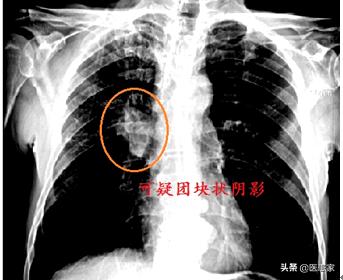

実際、人それぞれ腫瘍は異なり、病期分類によって腫瘍の進展速度も異なります。その結果、腫瘍が急速に成長し、数カ月で大きく成長するケースもあれば、3~5年ではほとんど成長しないケースもある。しかし、一般の人が腫瘍の発育が非常に早いと感じるのは、単純に発見後、多くの人が通常中期、あるいは後期であるため、発見から命がなくなるまで油断していると感じることが多いからである。

ここで申し上げたいのは、がんが早期であれば、その進行はそれほど早くなく、治療も簡単で予後も良いということです。しかし、がんが進行していることに気づく人が多いのは、普段、体調が悪くないのに検診に行かず、3~5年も検診を受けず、不快な症状が出て初めて検診に行こうと考えるからです。しかし、症状が現れたときには、最適な治療時期を逃していることが多い。

したがって、可能であれば定期健診、できれば年1回の健診を怠ってはならない。45歳以上の人や、粉塵や化学物質が多い職場環境の人は、早期発見・早期治療のためにも半年に一度は人間ドックを受けた方がいいし、腫瘍は実はそれほど怖いものではない。